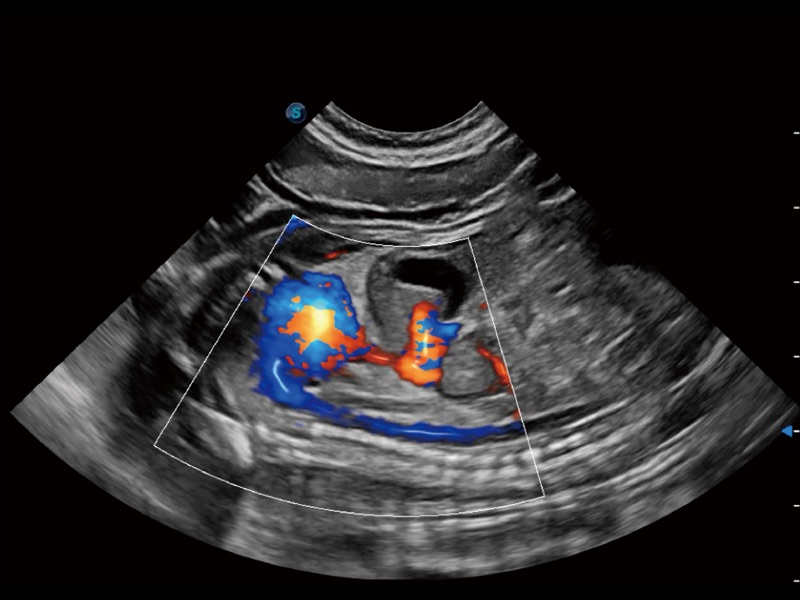

(犬)髂动脉血流

(犬)胎儿主动脉弓立体血流

• Micro F 显微血流成像

通过创新的 Matrix E自适应滤波器和超长时间域算法,极大提升超低速微细血流的检出能力,同时更精准地滤除软组织和噪声信号,为兽用医生提供以往无法通过常规血流获得的疾病诊断信息。

• 宽景成像

通过色彩血流和实时宽景相结合,可观察到完整的静脉或动脉的血流,方便医生检查。实时扫查过程中,如有任何操作失误也可以很容易地进行回扫擦除,而不会中断扫查。